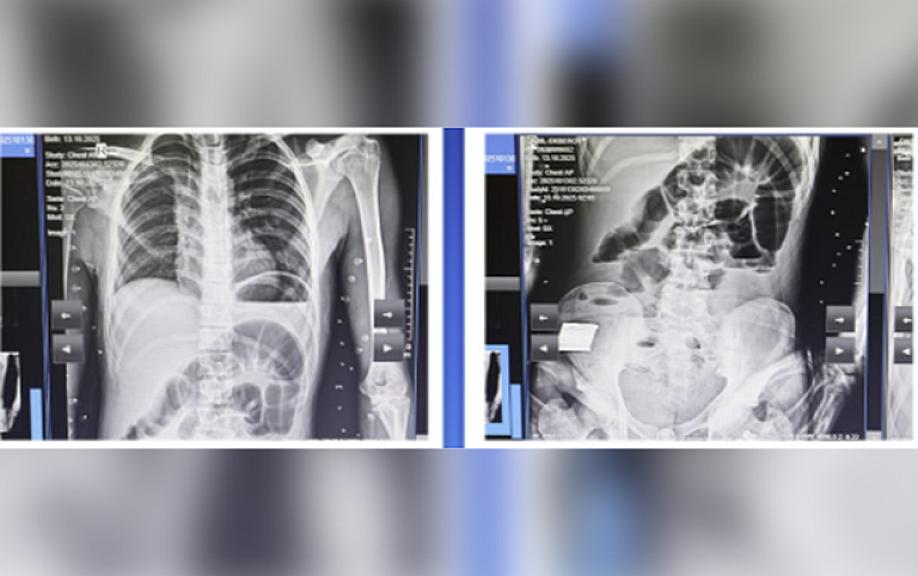

Bildirilib ki, oktyabrın 14-ü 2008-ci il təvəllüdlü yeniyetmə qarın nahiyəsində kəskin ağrı, ürəkbulanma, təkrarlanan qusma və hipertermiya şikayətləri ilə Kliniki Tibbi Mərkəzin Təcili və təxirəsalınmaz tibbi yardım şöbəsinə gətirilib: “Müayinələr nəticəsində xəstəyə peritonit diaqnozu qoyulub və əməliyyatönü hazırlıqdan sonra təxirəsalınmaz cərrahi müdaxilə aparılıb. Həkimlər tərəfindən nazik bağırsaq seqmentinin rezeksiyası, yoğun bağırsağın defektinin tikilməsi əməliyyatı icra olunub.

Əməliyyat zamanı nazik bağırsaqda, iliosekal küncdən 70-80 sm məsafədə, iki yerdə deşici (perforativ) zədələnmə müəyyən olunub. Bu perforasiyalara səbəb bağırsaq mənfəzində yerləşən iti və sərt yad cisim taxta parçası olub. Bundan əlavə, yoğun bağırsaqda da perforativ dəlik və bütün nazik bağırsaq boyunca mənfəz daxilində müxtəlif ölçülü, iti uclu, sərt yad cisimlər aşkarlanıb”.

Qeyd olunub ki, uğurlu cərrahi müdaxilə və 8 günlük stasionar müalicə nəticəsində xəstənin vəziyyəti kafi qiymətləndirilib və o, ambulator müalicə üçün evə buraxılıb.